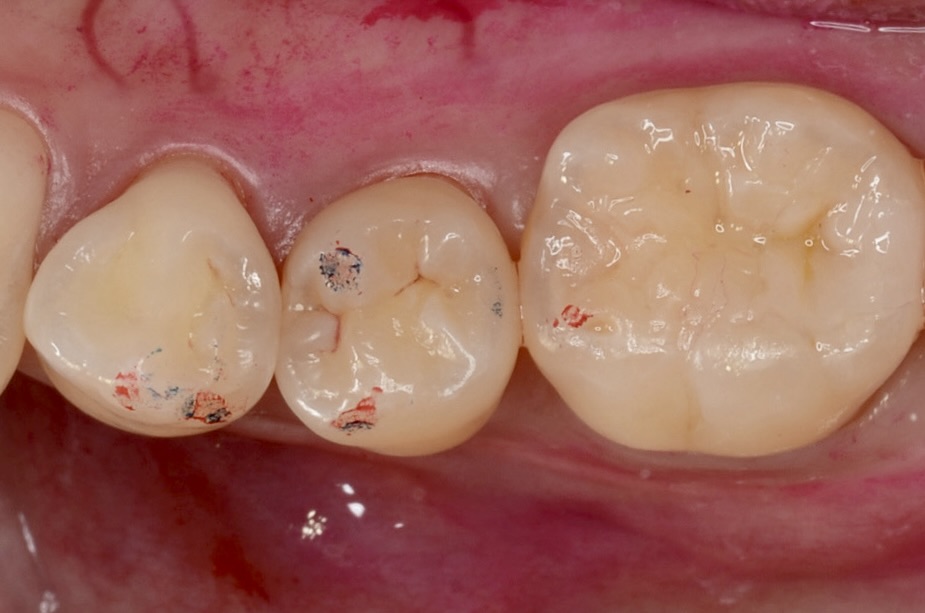

Before

| 年齢 | 40代 | 治療方法 | ダイレクトボンディング |

| 性別 | 女性 | 通院回数 | 2回 |

| 主訴 | できるだけ歯を削る量を少なくしてむし歯を治したい | 費用 |

115,500円(税込) |

調布市からお越しの患者さんです。できるだけ健康な歯を削らない治療を希望され下高井戸デンタルオフィスを受診されました。